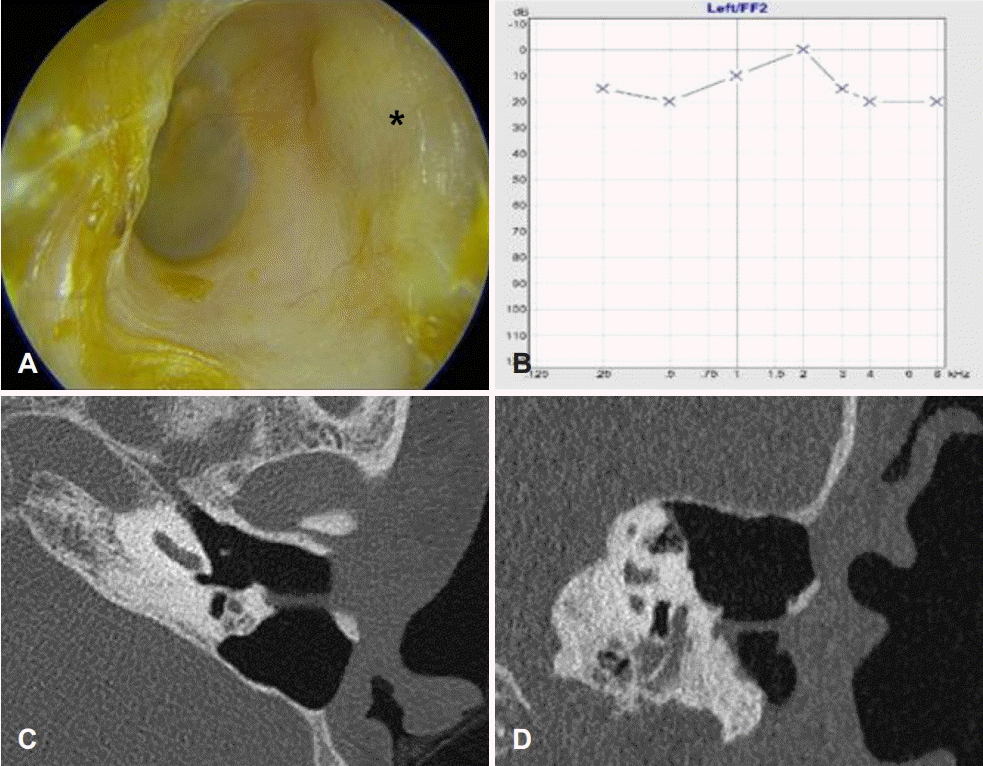

50세 여자 환자가 1년 전부터 시작된 좌측 귀 이충만감과 간헐적인 측두부 두통을 주소로 내원하였다. 외상 등의 병력이나 난청과 이통 등 다른 이과적 증상은 없었다. 이학적 검사상 좌측 골성 외이도 후방의 중앙에 지름 약 10 mm 가량의 결손부가 관찰되었고 결손부를 통해 유양돌기 내부가 노출되어 있었다(Fig. 1A). 양측 고막은 정상소견이었고 순음청력검사에서 6분법상 좌측 청력역치는 20 dB였고 어음명료도 검사상 100%의 정상소견이었다(Fig. 1B). 전산화단층촬영상 좌측 골부 외이도 후벽에 결손이 관찰되었고 결손에 인접한 유양돌기의 부분적인 소실이 관찰되었으나 유양돌기 내 점막은 정상으로 판단되었다(Fig. 1C and D). 좌측 골부 외이도 후벽의 결손으로 진단되었으나 정상 청력이며 감염 등 동반 증상이 없어 3-6개월의 주기적인 경과 관찰을 시행했다.

Initial findings of the patient. A and B: Transcanal endoscopic view shows a defect (black asterisk) in posterior wall of left bony external auditory canal (bEAC) with exposed mastoid cavity and normal tympanic membrane (A) pure tone audiogram (B) shows normal hearing threshold. C and D: CT of the left temporal bone reveals the large defect (white asterisks) in posterior wall of bEAC with clear mastoid cavity.